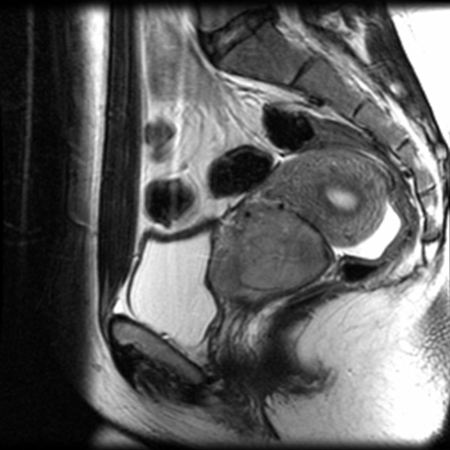

MRI for treatment planning

From the collection of Neil S. Horowitz, MD; used with permission

See this image in context in the following section/s:

Cervical cancer